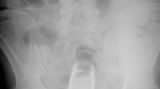

Die Webseite radiopaedia.org zeigt, welche Dinge Ärzte auf Röntgenbildern schon entdeckt haben. Die Aufnahmen wirken skurril und erschreckend zugleich und machen deutlich, wie weit die eingeführten Dinge bereits in den mescnhlichen Darm vordringen können.

Aber Glück im Unglück für die Patienten: Die Gegenstände können meist ohne Operation entfernt werden. Sehen Sie hier einige der spektakulärsten Röntgenaufnahmen. Da runzeln selbst Chirurgen die Stirn.